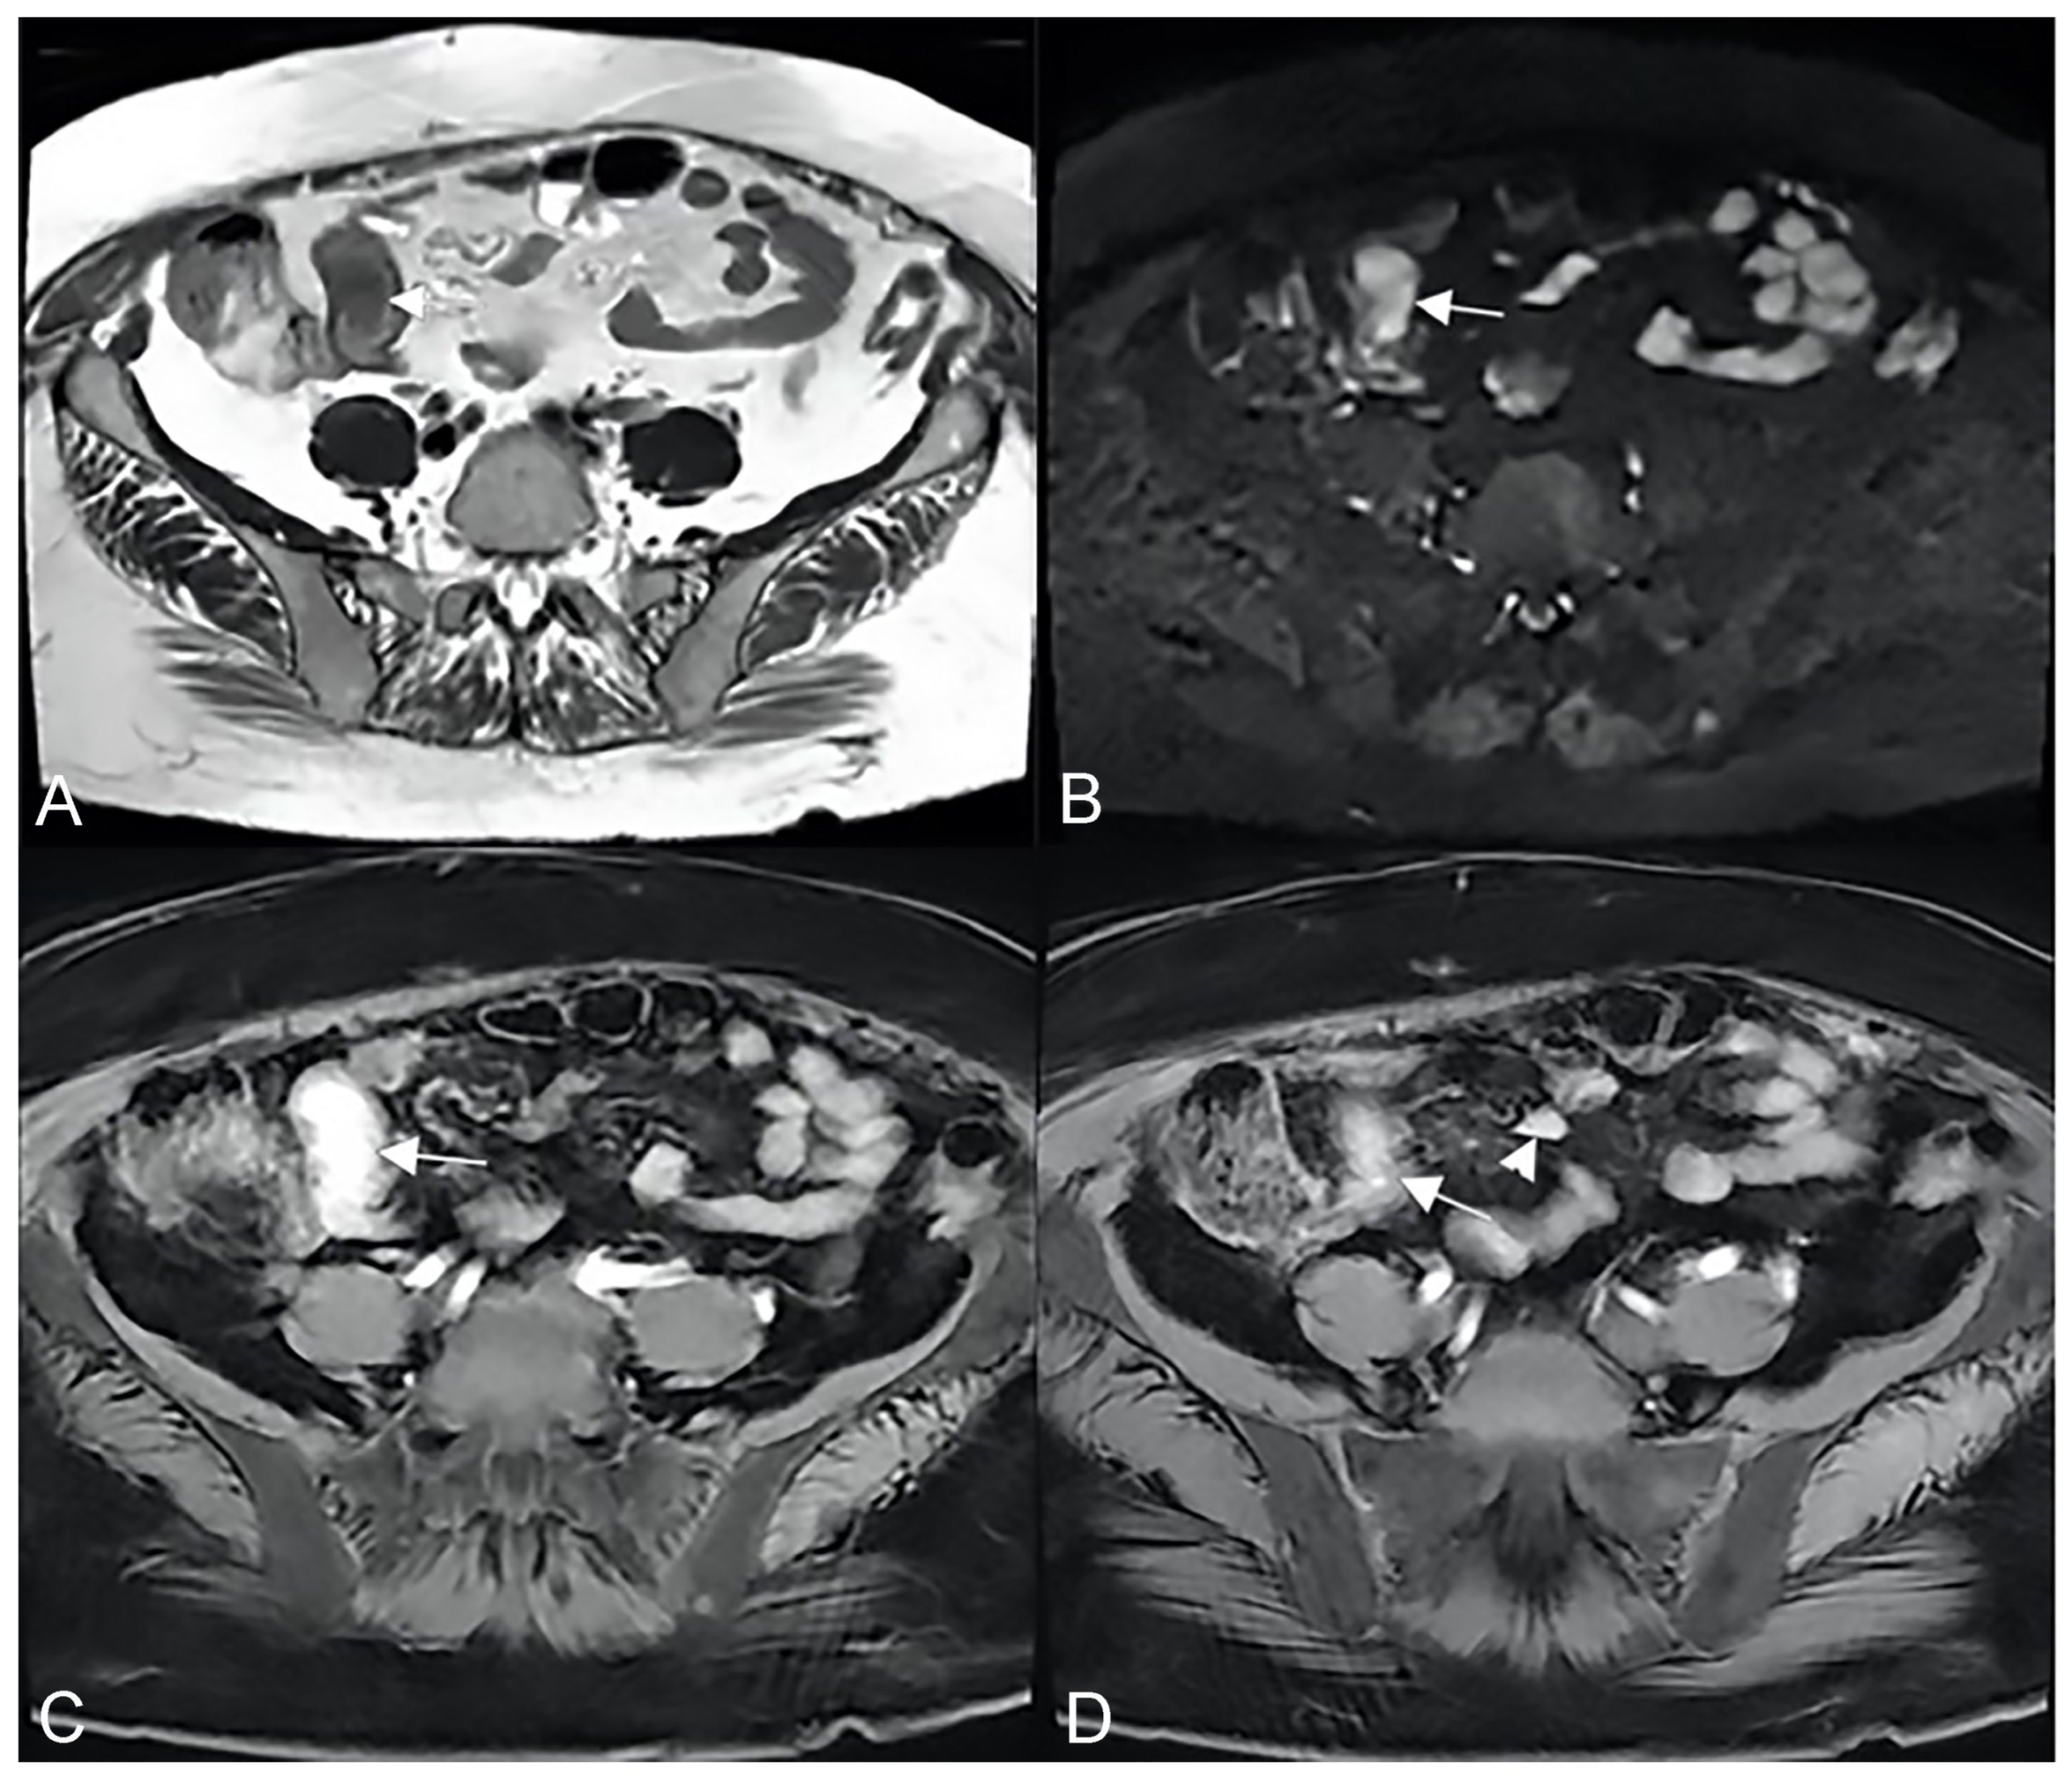

Another possible imaging findings of mesenteric inflammation is an abscess that appears as the usual appearance of an encapsulated collection with a rim enhancement and/or a central zone containing air or necrotic material. Moreover, MRE may show perienteric edema/inflammation as a high T2-W signal or a restricted diffusion in the mesenteric fat adjacent to abnormal bowel loops and the engorged vasa recta that supply an inflamed bowel loop (“comb sign”) [6] (Figure 15).

Figure 15.

During the active phase, the vascularization of the mesenteric fan increases with an evident engorgement of the vasa recta that takes on the appearance of a clear palisade that stands out against the background of the hypertrophic mesentery. According to some, this aspect commonly resembles the teeth of a hair comb (comb sign) but which we like to imagine instead, due to the thickness of the hypertrophic vasa recta, as a palisade of a fence (mesentery fence). (A,B,D,E): Coronal fast imaging employing steady-state acquisition (FIESTA) image, (C): coronal contrast-enhanced fat-suppressed T1-weighted maximum intensity projection image, and (F): coronal contrast-enhanced fat-suppressed T1-weighted image show engorgement of the vasa recta (yellow arrowheads in (A–F) images.